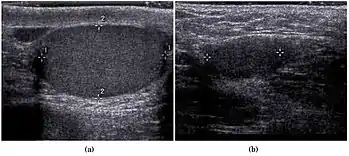

In the minority of cases with bilaterally nonpalpable testes, further testing to locate the testes, assess their function, and exclude additional problems is often useful. Scrotal ultrasound or magnetic resonance imaging performed and interpreted by a radiologist can often locate the testes while confirming absence of a uterus. At ultrasound, the undescended testis usually appears small, less echogenic than the contralateral normal testis and usually located in the inguinal region. With color Doppler ultrasonography, the vascularity of the undescended testis is poor.